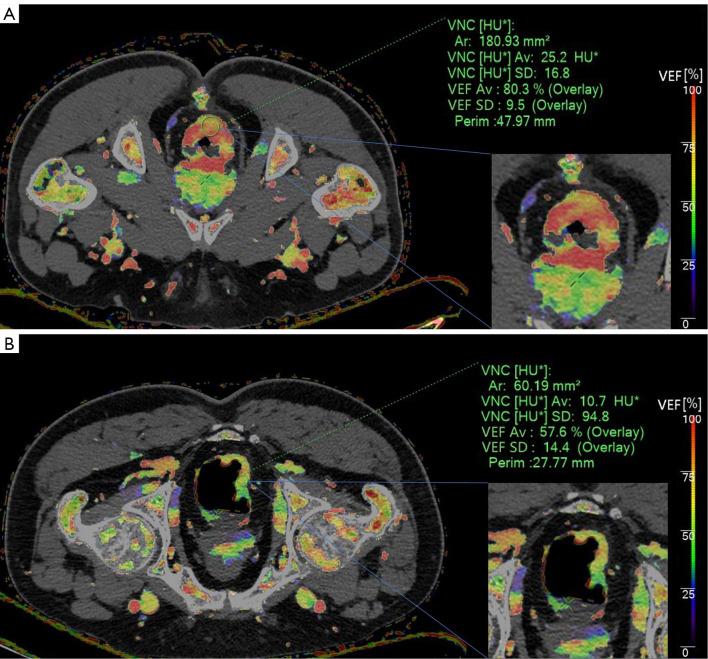

Consecutive patients suspected of having CRC and with a clinical indication for enhanced CT from April 2021 to July 2022 at a single institution were prospectively enrolled to undertake spectral CT scanning. The spectral features were extracted by two reviewers and intraclass correlation coefficient (ICC) was used for interobserver agreement evaluation. A total of 16 spectral parameters, including unenhanced effective atomic number, triphasic iodine concentrations (ICs)/normalized ICs (NICs)-/1/NIC-/spectral curve slopes (λ-), two arterial enhancement fractions (AEFs), and venous enhancement fraction (VEF), were determined for analysis. Patients with and without VEDM after surgery were matched using propensity score matching (PSM). The diagnostic performance was assessed using the area under the curve (AUC). Models of multiple modalities were generated.

In total, 222 patients were included (141 males, age range, 32-83 years) and 13 patients developed VEDM. Interobserver agreement ranged from good to excellent (ICC, 0.773-0.964). A total of three spectral parameters (VEF, λ-, and 1/NIC-) exhibited significant discriminatory ability (P<0.05) in predicting VEDM, with AUCs of 0.822 [95% confidence interval (CI): 0.667-0.926], 0.738 (95% CI: 0.573-0.866), and 0.713 (95% CI: 0.546-0.846) and optimal cutoff points of 67.16%, 2.46, and 2.44, respectively. The performance of these spectral parameters was validated in the entire cohort; the combined spectral model showed comparable efficiency to the combined clinical model [AUC, 0.771 (95% CI: 0.622-0.919) 0.779 (95% CI: 0.663-0.894), P>0.05]; the clinical-spectral model achieved further improved AUC of 0.887 (95% CI: 0.812-0.962), which was significantly higher than the combined clinical model (P=0.015), yet not superior to the combined spectral model (P=0.078).